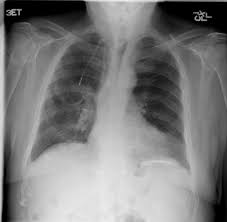

Pleural Plaques From Asbestos British Lung Foundation

Pleural Plaques From Asbestos British Lung Foundation from www.blf.org.uk